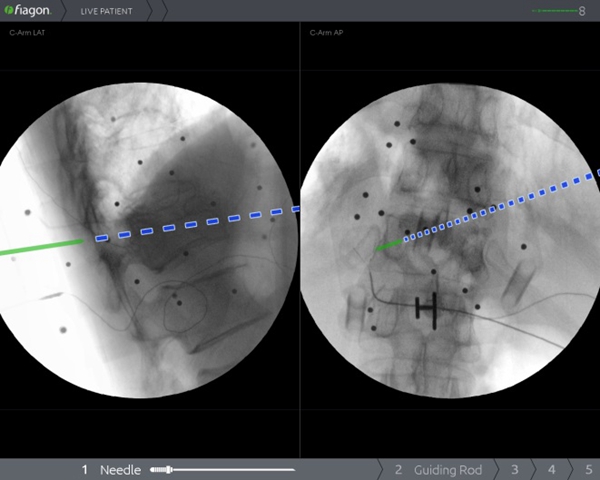

过去,受限于技术和设备,在脊柱上做手术,犹如在“暗箱”内操作,需要反复进行X线透视来判断术中状况,手术时间长,神经、血管损伤风险大。脊柱手术通常需要置入多枚螺钉,在没有先进设备辅助的情况下,医生只能凭经验操作,增加了相应的手术风险。脊柱手术的精准性和安全性一直是医生和患者最为关注的问题。而Joimax电磁导航系统作为目前世界最知名的导航系统,无传统光学导航系统“红外线遮挡”问题,并且不占用手术空间、可弯曲器械能实现尖端导航、定位器小巧,能实现多节段同步导航。骨二科(脊柱外科)李浩鹏主任表示,将导航系统应用于脊柱手术中,可以为医生呈现实时、直观的三维影像导航信息,帮助医生准确规划和及时更新手术方案,提高置钉的准确性,降低误伤神经、血管的风险,有效减少手术并发症,缩短住院时间,帮助患者及早恢复日常生活。

2020年1月9日,骨二科(脊柱外科)王栋教授团队成功将电磁导航技术引入到脊柱手术中,开展了医院首例电磁导航腰椎后方椎间融合术(PLIF)和首例电磁导航经皮穿刺椎体成形术(PVP)。手术当日,通过简单的安装信号发射器、定位仪并进行2D影像认证后,王栋教授团队在导航的辅助下,轻松完成原先脊柱手术中风险巨大的椎体植钉过程,随后的椎管减压及水泥注入等步骤一气呵成,有效缩短了手术时间、术中投射次数,大大降低了手术风险。